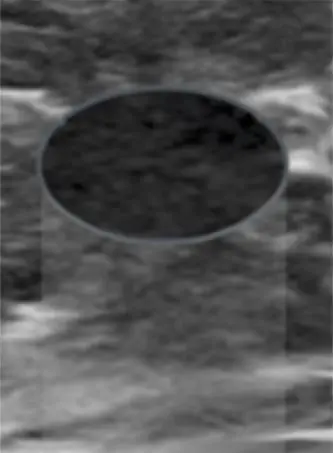

섬유선종(Fibroadenoma)

저에코성

보통 타원형 또는 원형(간혹 분엽형)

경계가 뚜렷한 가장자리

수평 방향

가끔 미세한 후방 에코 증강간혹 큰 석회화 발견